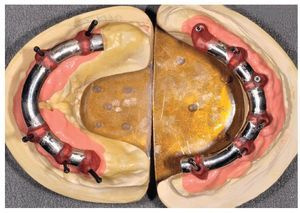

Figs. 101 y 102. Vista lateral de las estructuras atornilladas sobre los modelos.

Figs. 103 a 105. Recubrimiento estético de las estructuras con dientes protésicos prefabricados de composite. Vista frontal y lateral a derecha e izquierda.